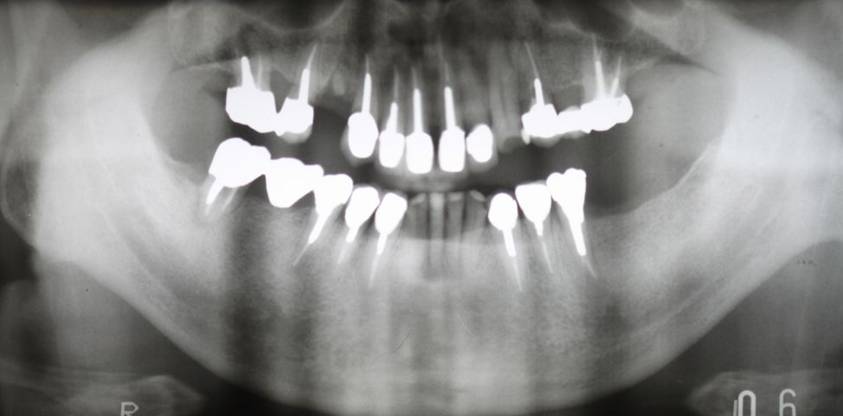

術前のパノラマレントゲン写真。仮歯を支えている4本の歯は根が残っているだけで抜歯の必要がありました。

63歳術後のパノラマレントゲン。インプラントはスプラインツイスト

術前パノラマレントゲン写真。根の周りが黒くなり、骨がなくなっていることがわかります